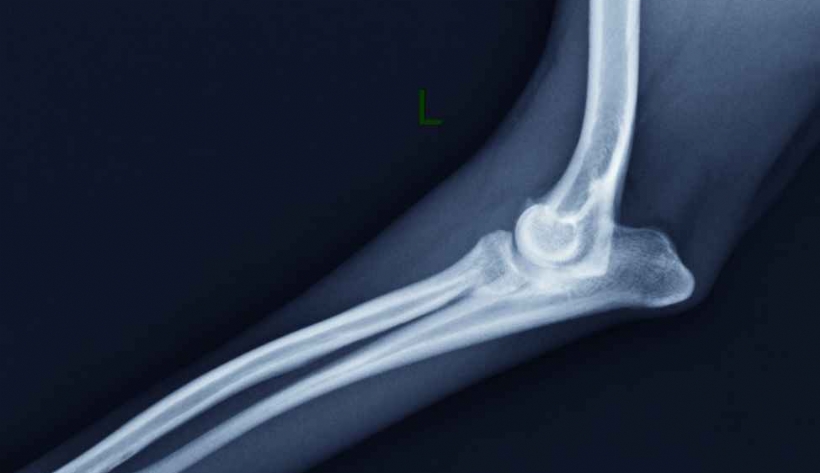

Mercredi 11 Fevrier 2026 Animaux de compagnieRadiographie de profil de l'articulation du coude gauche d'un chien présentant un syndrome du radius court.

Le syndrome du radius court est une anomalie radio-ulnaire observée chez les chiots en croissance et les adultes, pouvant provoquer une incongruence au niveau du coude ainsi qu'une subluxation de la tête radiale. Cette affection entraîne une sollicitation...